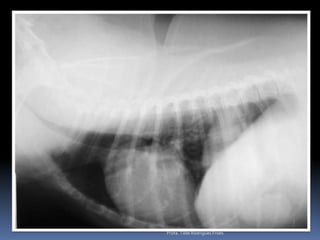

Animal: Flick, canino, macho, Poodle, 10 anos - TosseProfa. Tilde Rodrigues Froes

Exame radiográfico torácicoNossa rotina – nossos velhinhos...Pesquisa de metástasesColapso de traquéiaInsuficiência cardíacaBronquite crônica *Análise interobservadorSempre mais de um observador analisa o filme radiográfico torácico (difícil) Profa. Tilde Rodrigues Froes

Ex colapsoProfa. Tilde Rodrigues Froes